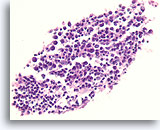

Afbeelding 16

Benigne, hyperplastisch/adenomatoïde nodule, schildklier FNA, celblok.

Dun colloïde linksonder vergeleken met het dichtere colloïde in de microfollikels pleit samen met het afgeplatte, atrofische uiterlijk van de folliculaire cellen in de microfollikels voor een benigne hyperplastische/adenomatoïde nodule.

40X

Afbeelding 16

Benigne, hyperplastisch/adenomatoïde nodule, schildklier FNA, celblok.

Dun colloïde linksonder vergeleken met het dichtere colloïde in de microfollikels pleit samen met het afgeplatte, atrofische uiterlijk van de folliculaire cellen in de microfollikels voor een benigne hyperplastische/adenomatoïde nodule.

40X